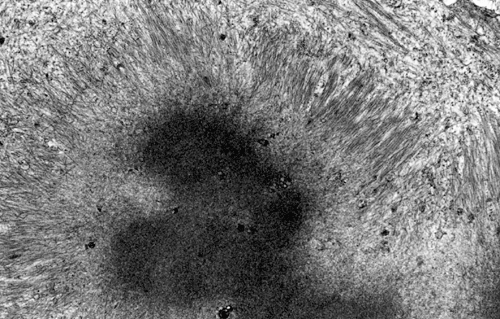

On hematoxylin-eosin stained sections, there is an increased variation of fiber diameter with many atrophic fibers intermingled with fibers of normal caliber. There is no evidence of fiber grouping or perifascicular atrophy. No inflammatory cells are present. There is also mild interstitial fibrosis (Panel A). On higher magnification, many fibers have a round concentric structure (Panel B). Irregular, centrally located depositions are also identified on modified Gomori's trichrome. The concentric nature, however, is not as obvious as in the hematoxin-eosin stained sections (Panel C). Type I and II fibers are not clearly separated in the ATPase preparation at pH 9.4. This is a common situation in chronically ill muscle (Panel D). The type I fibers are unusually dark. There is an increase in the proportion of type I fibers. The atrophic fibers are usually type II fibers. The concentric lesions are found predominantly in type I fibers (Panel E). There is an increase in PAS staining which is consistent with increased glycogen storage (Panel F). No increase in lipid content is demonstrated by oil red O (Panel G). On NADH-TR reaction, the concentric structures appear to have a clear central core that is devoid of enzymatic activity, a rim with intense enzymatic activity and a surround zone with relatively normal reactivity. These features are classic for target fibers (Panel H and I). No deficiency of laminin-2 (merosin) (Panel J) or dystrophin (Panel K) is demonstrated by immunohistochemistry. The central lesions are also immunoreactive for both laminin-2 and dystrophin. Immunohistochemistry for desmin demonstrate a core of strong immunoreactivity and also strong reaction in the sarcoplasmic membrane (Panel L and M). The target structures are also well demonstrated on semithin sections (Panel N). On electron microscopy, z-disc streaming is a common finding and they are often admixed with a substantial amount of dense granular electron dense substance (Panel O and P). There are also numerous cytoplasmic bodies characterized by radiating intermediate filaments (spheroid bodies) (Panel Q and R).